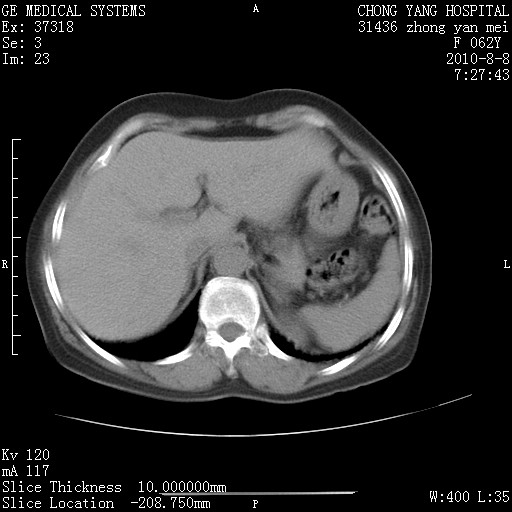

标题: CT28269:F62Y咳嗽胸痛数月。 [打印本页]

标题: CT28269:F62Y咳嗽胸痛数月。

两肺弥漫性间质纤维化伴继发性支扩。

考虑特发性肺间质纤维化

考虑两肺间质性肺炎并肺间质纤维化。

双肺间质纤维化合并感染、肺气肿

双肺间质纤维化

两肺间质纤维化并牵拉性细支气管扩张。

考虑两肺间质性肺炎并肺间质纤维化,肺气囊形成。

两肺间质改变,纵隔淋巴结肿大,需要考虑结节病的可能。